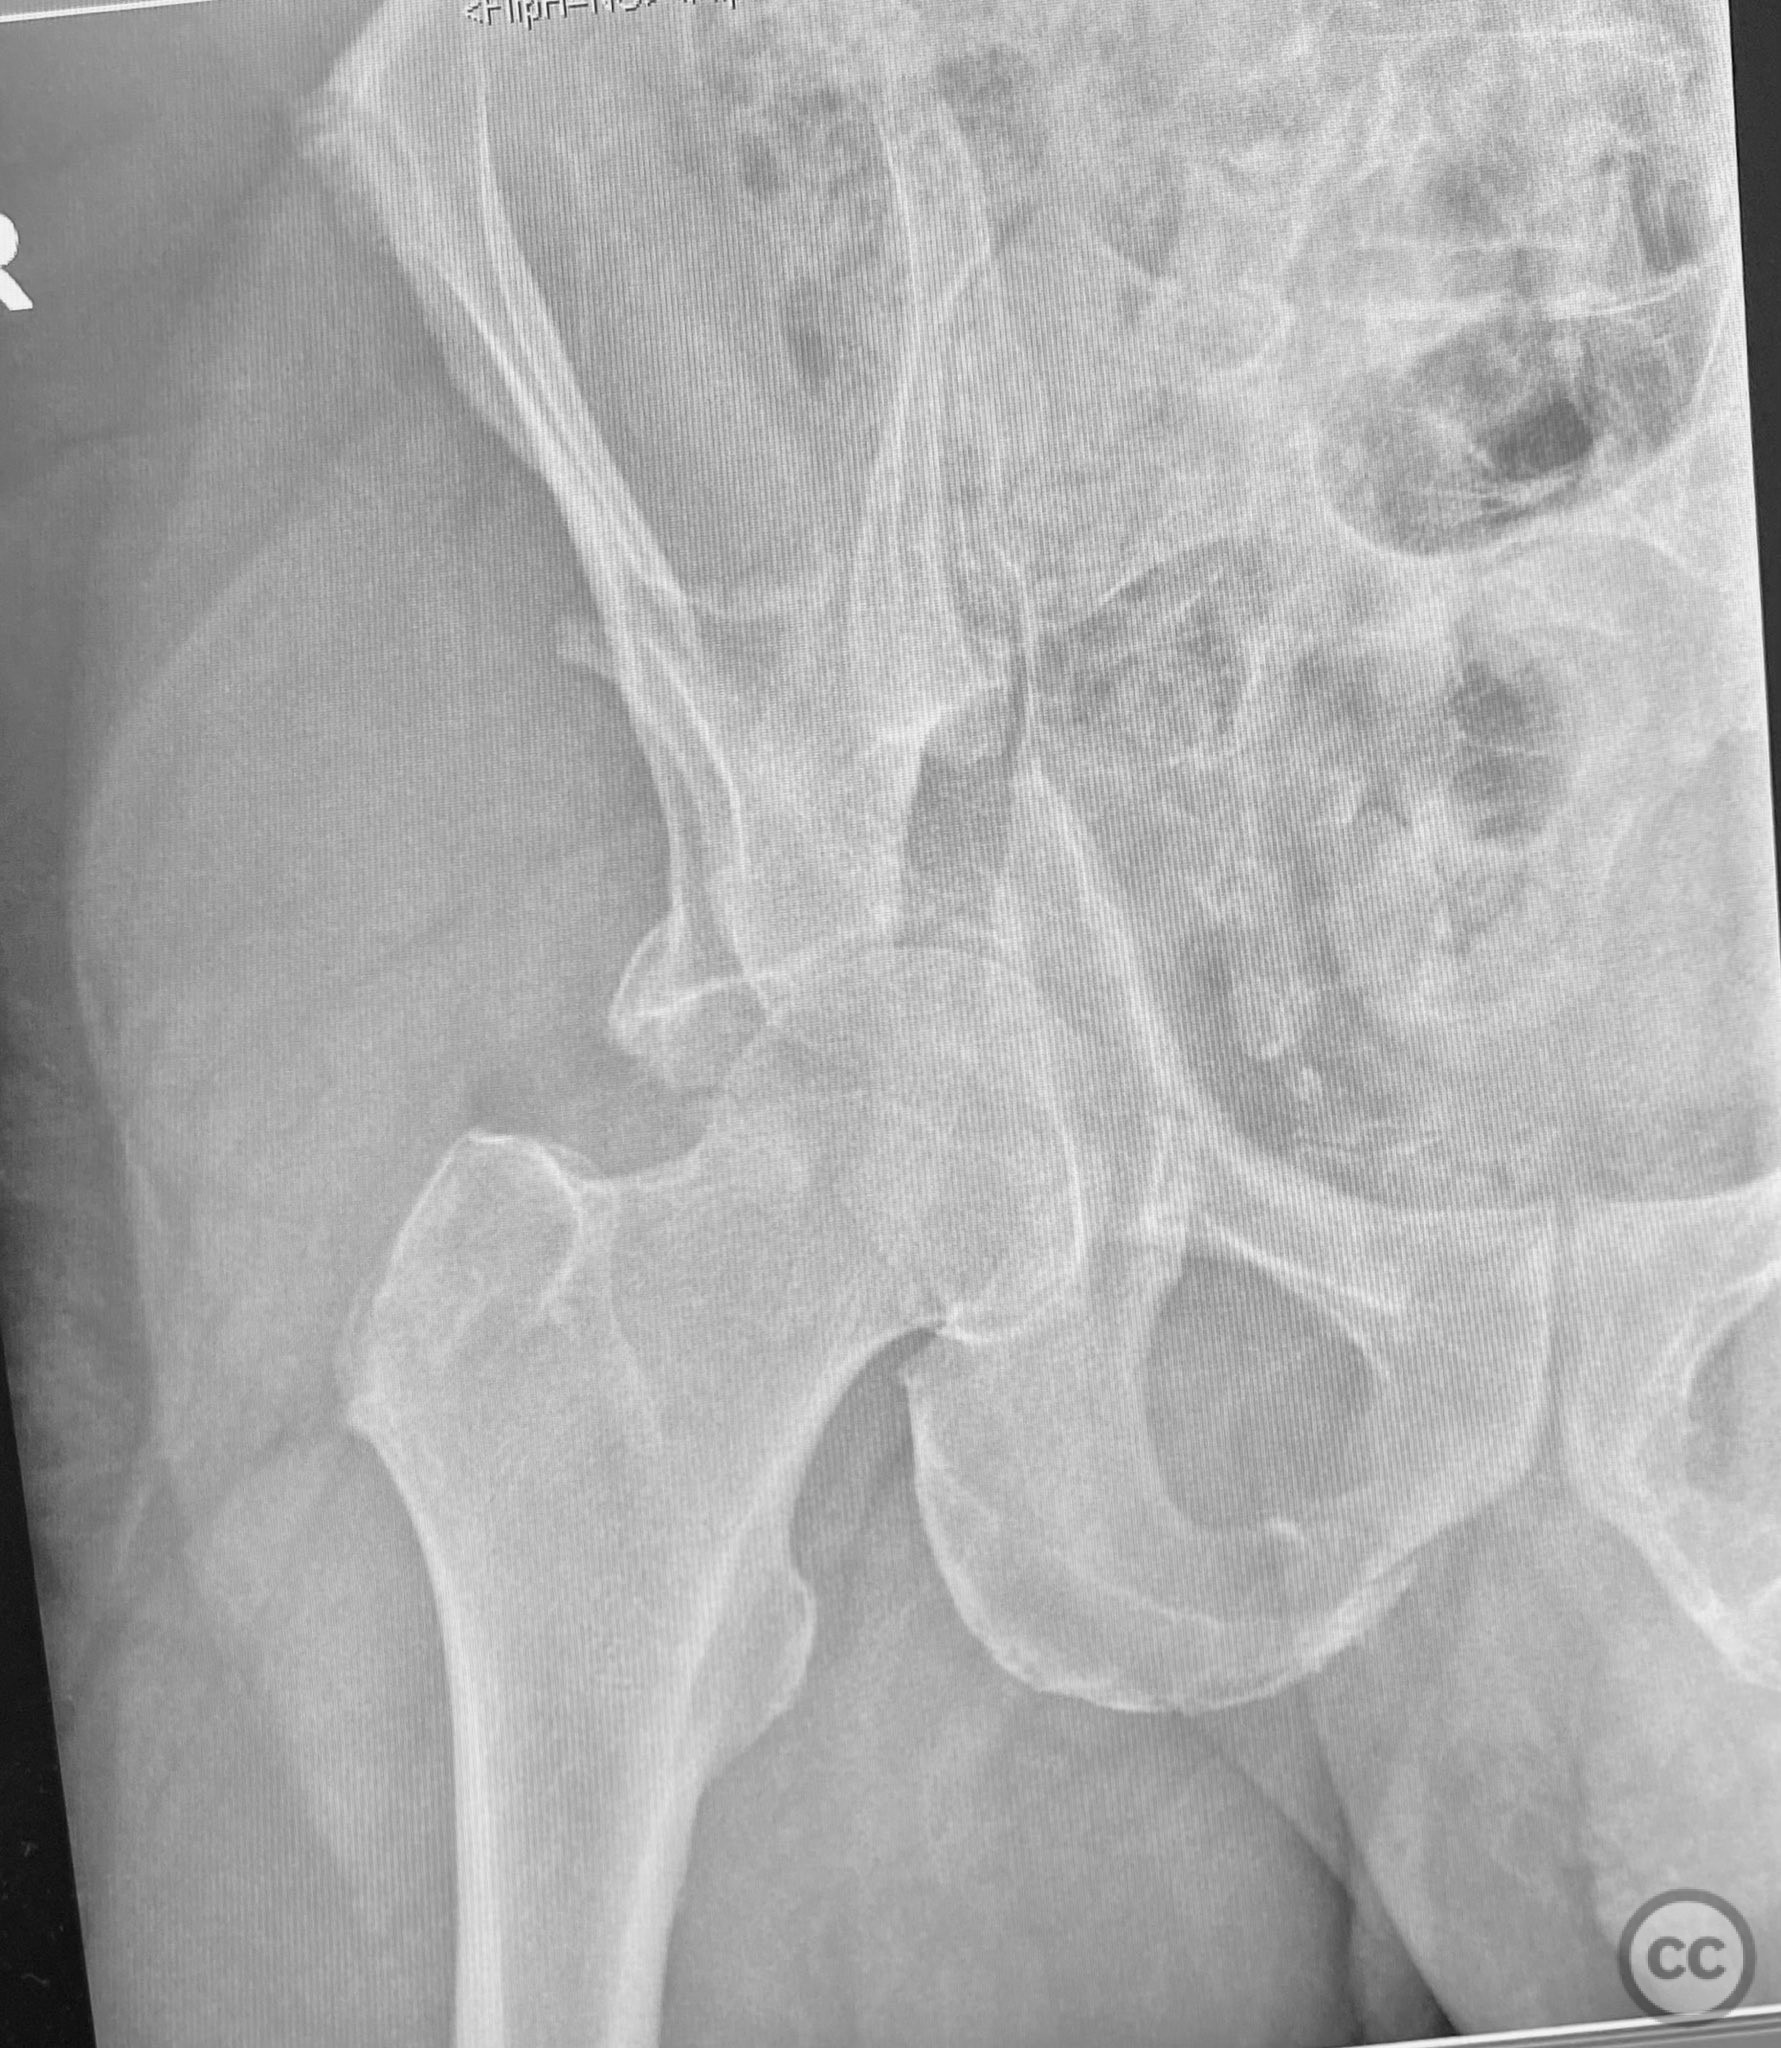

Clinical and radiological findings:  A patient presented with a combined anterior column and posterior hemi-transverse (AC/PHTr) acetabular fracture. Plain radiographs demonstrated multiple displaced fragments involving the acetabular dome and femoral head region, with clear disruption of the anterior column and posterior transverse components. Advanced imaging, including axial and coronal CT, provided detailed visualization of cortical surface displacement, fragment orientation, and associated soft tissue status. The edge of the intact dome and femoral head injuries were identified, as well as a residual defect at the edge of the dome following reduction. AO/OTA classification: 62B2 (anterior column with posterior hemitransverse).